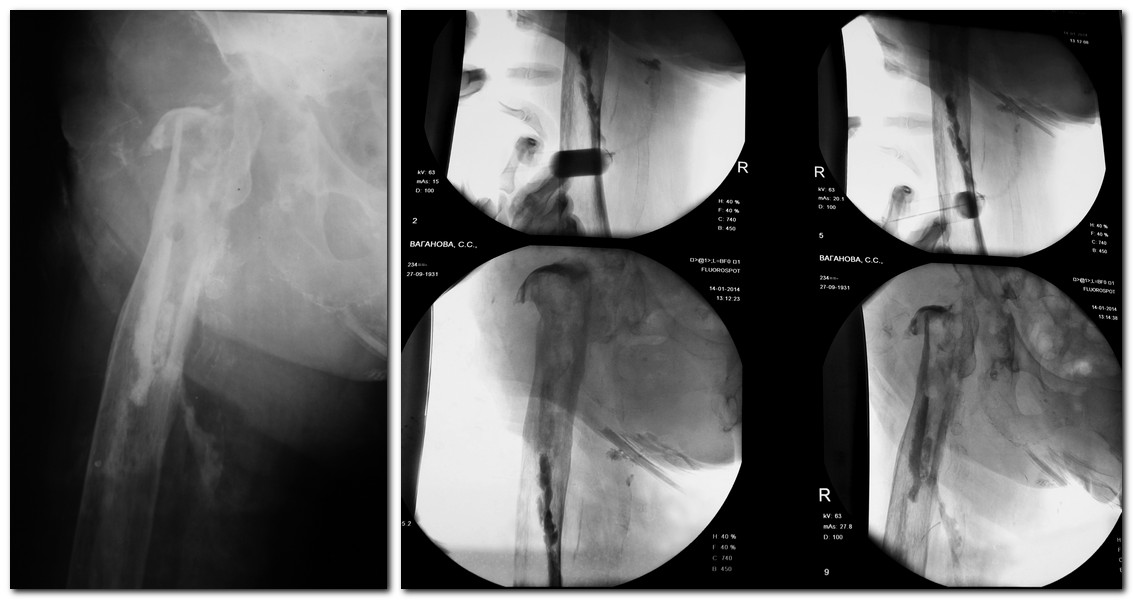

Уважаемые коллеги! Нужен совет по тактике дальнейшего лечения. Больная,83 лет. Поздняя глубокая парапротезная инфекция,нестабильность обоих компонентов. Свищи функционировали года 1,5. 1 в н/3 п/о раны, второй открылся около года по задней поверхности бедра на границе с/3 и н/3. Высевалась микст инфекция Г- и Г+. Мигрировал вертлужный компонент вверх. Не могли убрать долго протез по социальным делам. Убрали в начале декабря. У нас уже 3 месяца. Из системных антибиотиков прошлись по всему больничному набору: линкомицин, цефтриаксон, ципрофлоксацин, ванкомицин, целапинем, еще что-то там уже не помню. Последний посев из верхнего свища 9.01 дал скудный рост ацинетобактер, там какие-то 3 колонии. Отделяемое скудное, больше из нижнего свища, из свища вверху гораздо меньше, какое-то серозное, иногда с кровью. Местно промывал 2% р-ром лавасепта, менял на пронтосан. сейчас хочу попробовать диоксидин, так как не знаю, чем еще промывать. Сделал фистулографию на неделе, картинку прикрепляю. Свищ судя по ней сообщается с костью. Ну и остатки цемента в канале. Обсуждал с з/о, так как свищ не закрывается, открыться на диафизе, трепанационное окно сделать, удалить остатки цемента, может задренировать канал? Отмыть все. Думаю, что трепанированная кость не заживет если ее на место уложить, а дефект большой будет. Ну и так как больная ходит у нас в ходунках, боюсь, это может привести к перелому. А не ходить ей нельзя, да она и не будет сидеть, довольно активная пациентка, в прошлом году только вышла на пенсию, профессор в каком то институте. Как то так. Подскажите по дальнейшей тактике, если можно. Эластичных ревизионных разверток для бедра нет. Инструментария с длинной ручкой для канала нет.